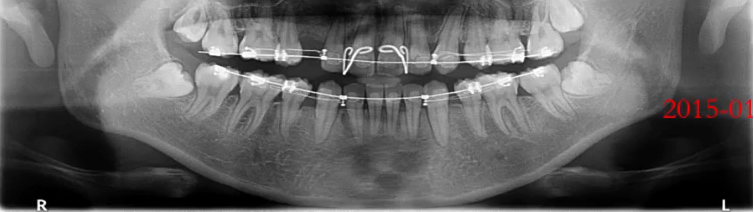

张XX,女,34岁

曲面断层片怎么看口腔精读 | 一次性教你看懂曲面断层片!_https://www.jmylbn.com_新闻资讯_第29张

1、牙槽骨水平性吸收,个别有垂直性吸收

2、全口结石影

治疗:洁刮治

检查:牙周探诊、咬合检查

正畸治疗考虑及设计

曲面断层片怎么看口腔精读 | 一次性教你看懂曲面断层片!_https://www.jmylbn.com_新闻资讯_第30张

3、牙缺失

治疗:种植治疗

检查:CBCT,对合牙

牙周治疗及维护

曲面断层片怎么看口腔精读 | 一次性教你看懂曲面断层片!_https://www.jmylbn.com_新闻资讯_第31张

4、智齿阻生

治疗:拔除

检查:颌骨评估、阻生齿评估、邻牙评估